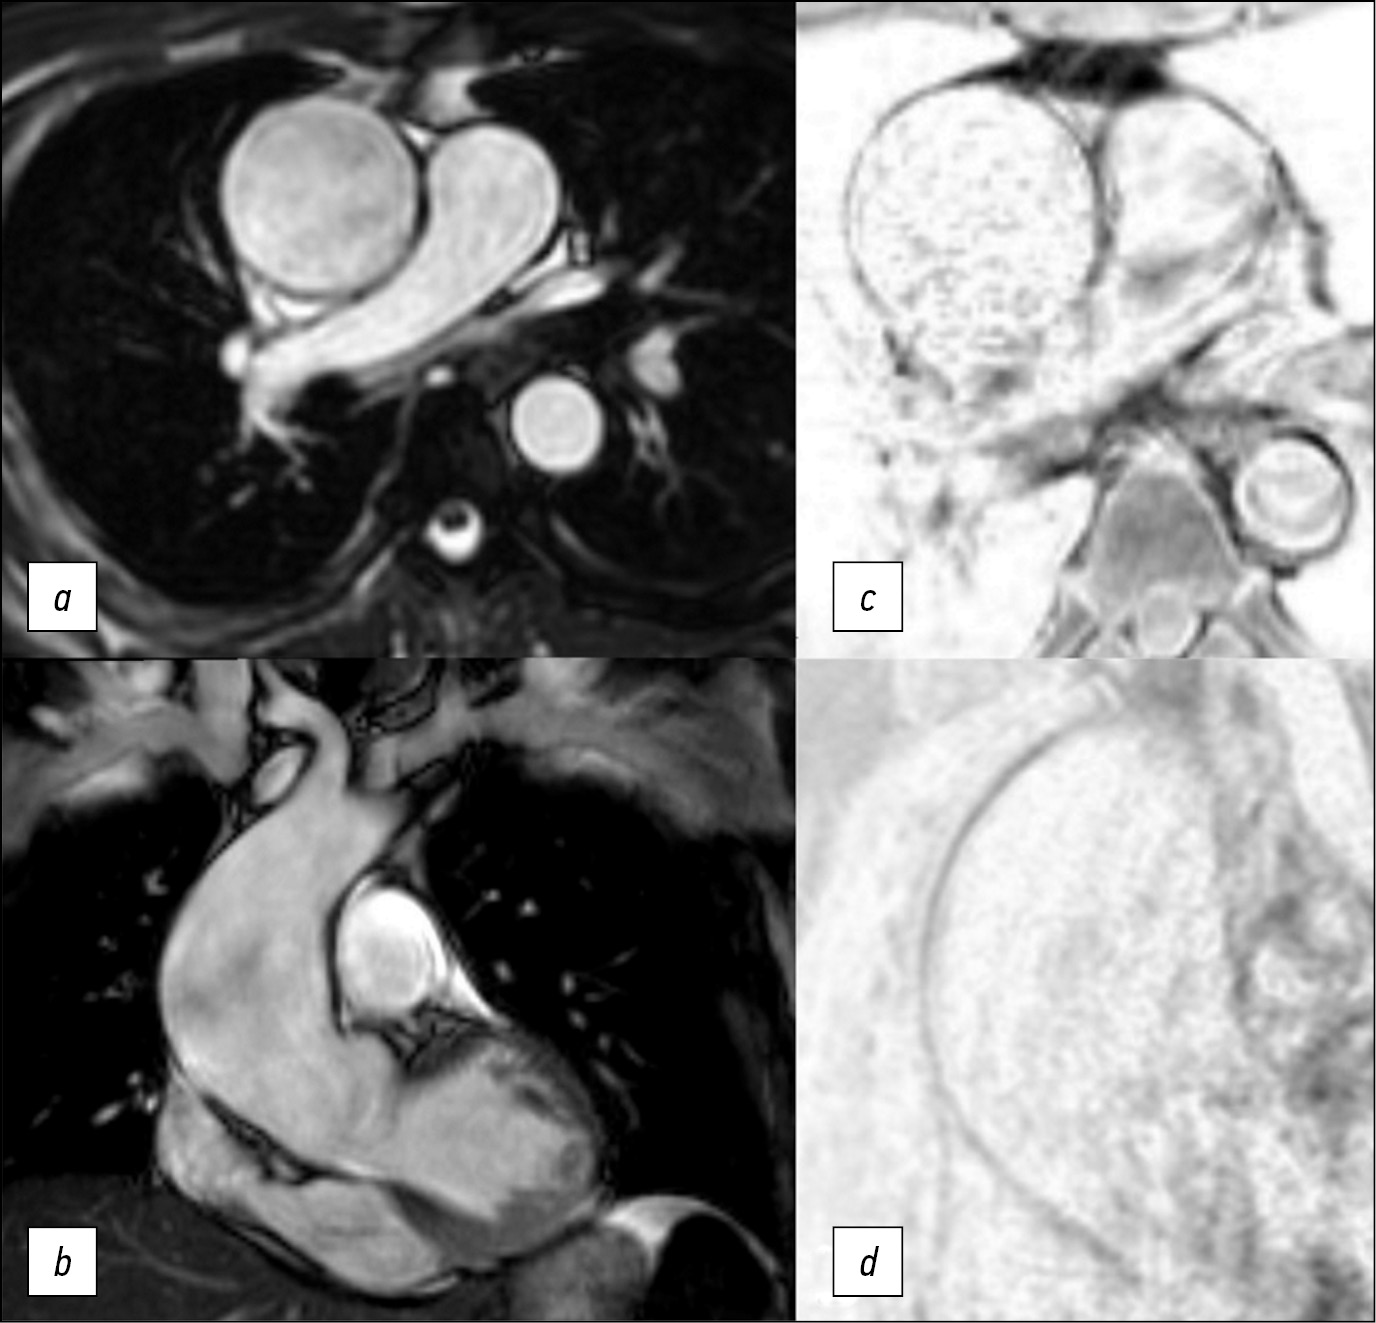

Diagnostic challenge: innovative approach in use of magnetic resonance imaging in aortic aneurysm

Abstract

Here we report a case of technological innovation: the use of magnetic resonance imaging to determine surgical strategy.

Here is a 47-year-old man who underwent an magnetic resonance imaging and subsequent surgical treatment of the aortic aneurysm. Unlike echocardiography, magnetic resonance imaging enabled us to view the entire thoracic aorta. Unlike computer tomography, magnetic resonance imaging enabled us to detect changes in the aortic wall accurately. Thus, in this case, the use of magnetic resonance imaging allowed us to determine the distal resection edge. The patient`s postoperative course was unremarkable. Use of electrocardiogram-synchronized magnetic resonance imaging of thoracic aorta allows detecting structural changes of the aortic wall and its mechanical properties. It is significant that magnetic resonance imaging results of the aortic wall correlate with histologic examination.

The extent of changes in the aortic wall must be determined to accurately plan surgical treatment of patients with aortic aneurism.

Magnetic resonance imaging of the aortic wall is promising for further study in multicenter research.